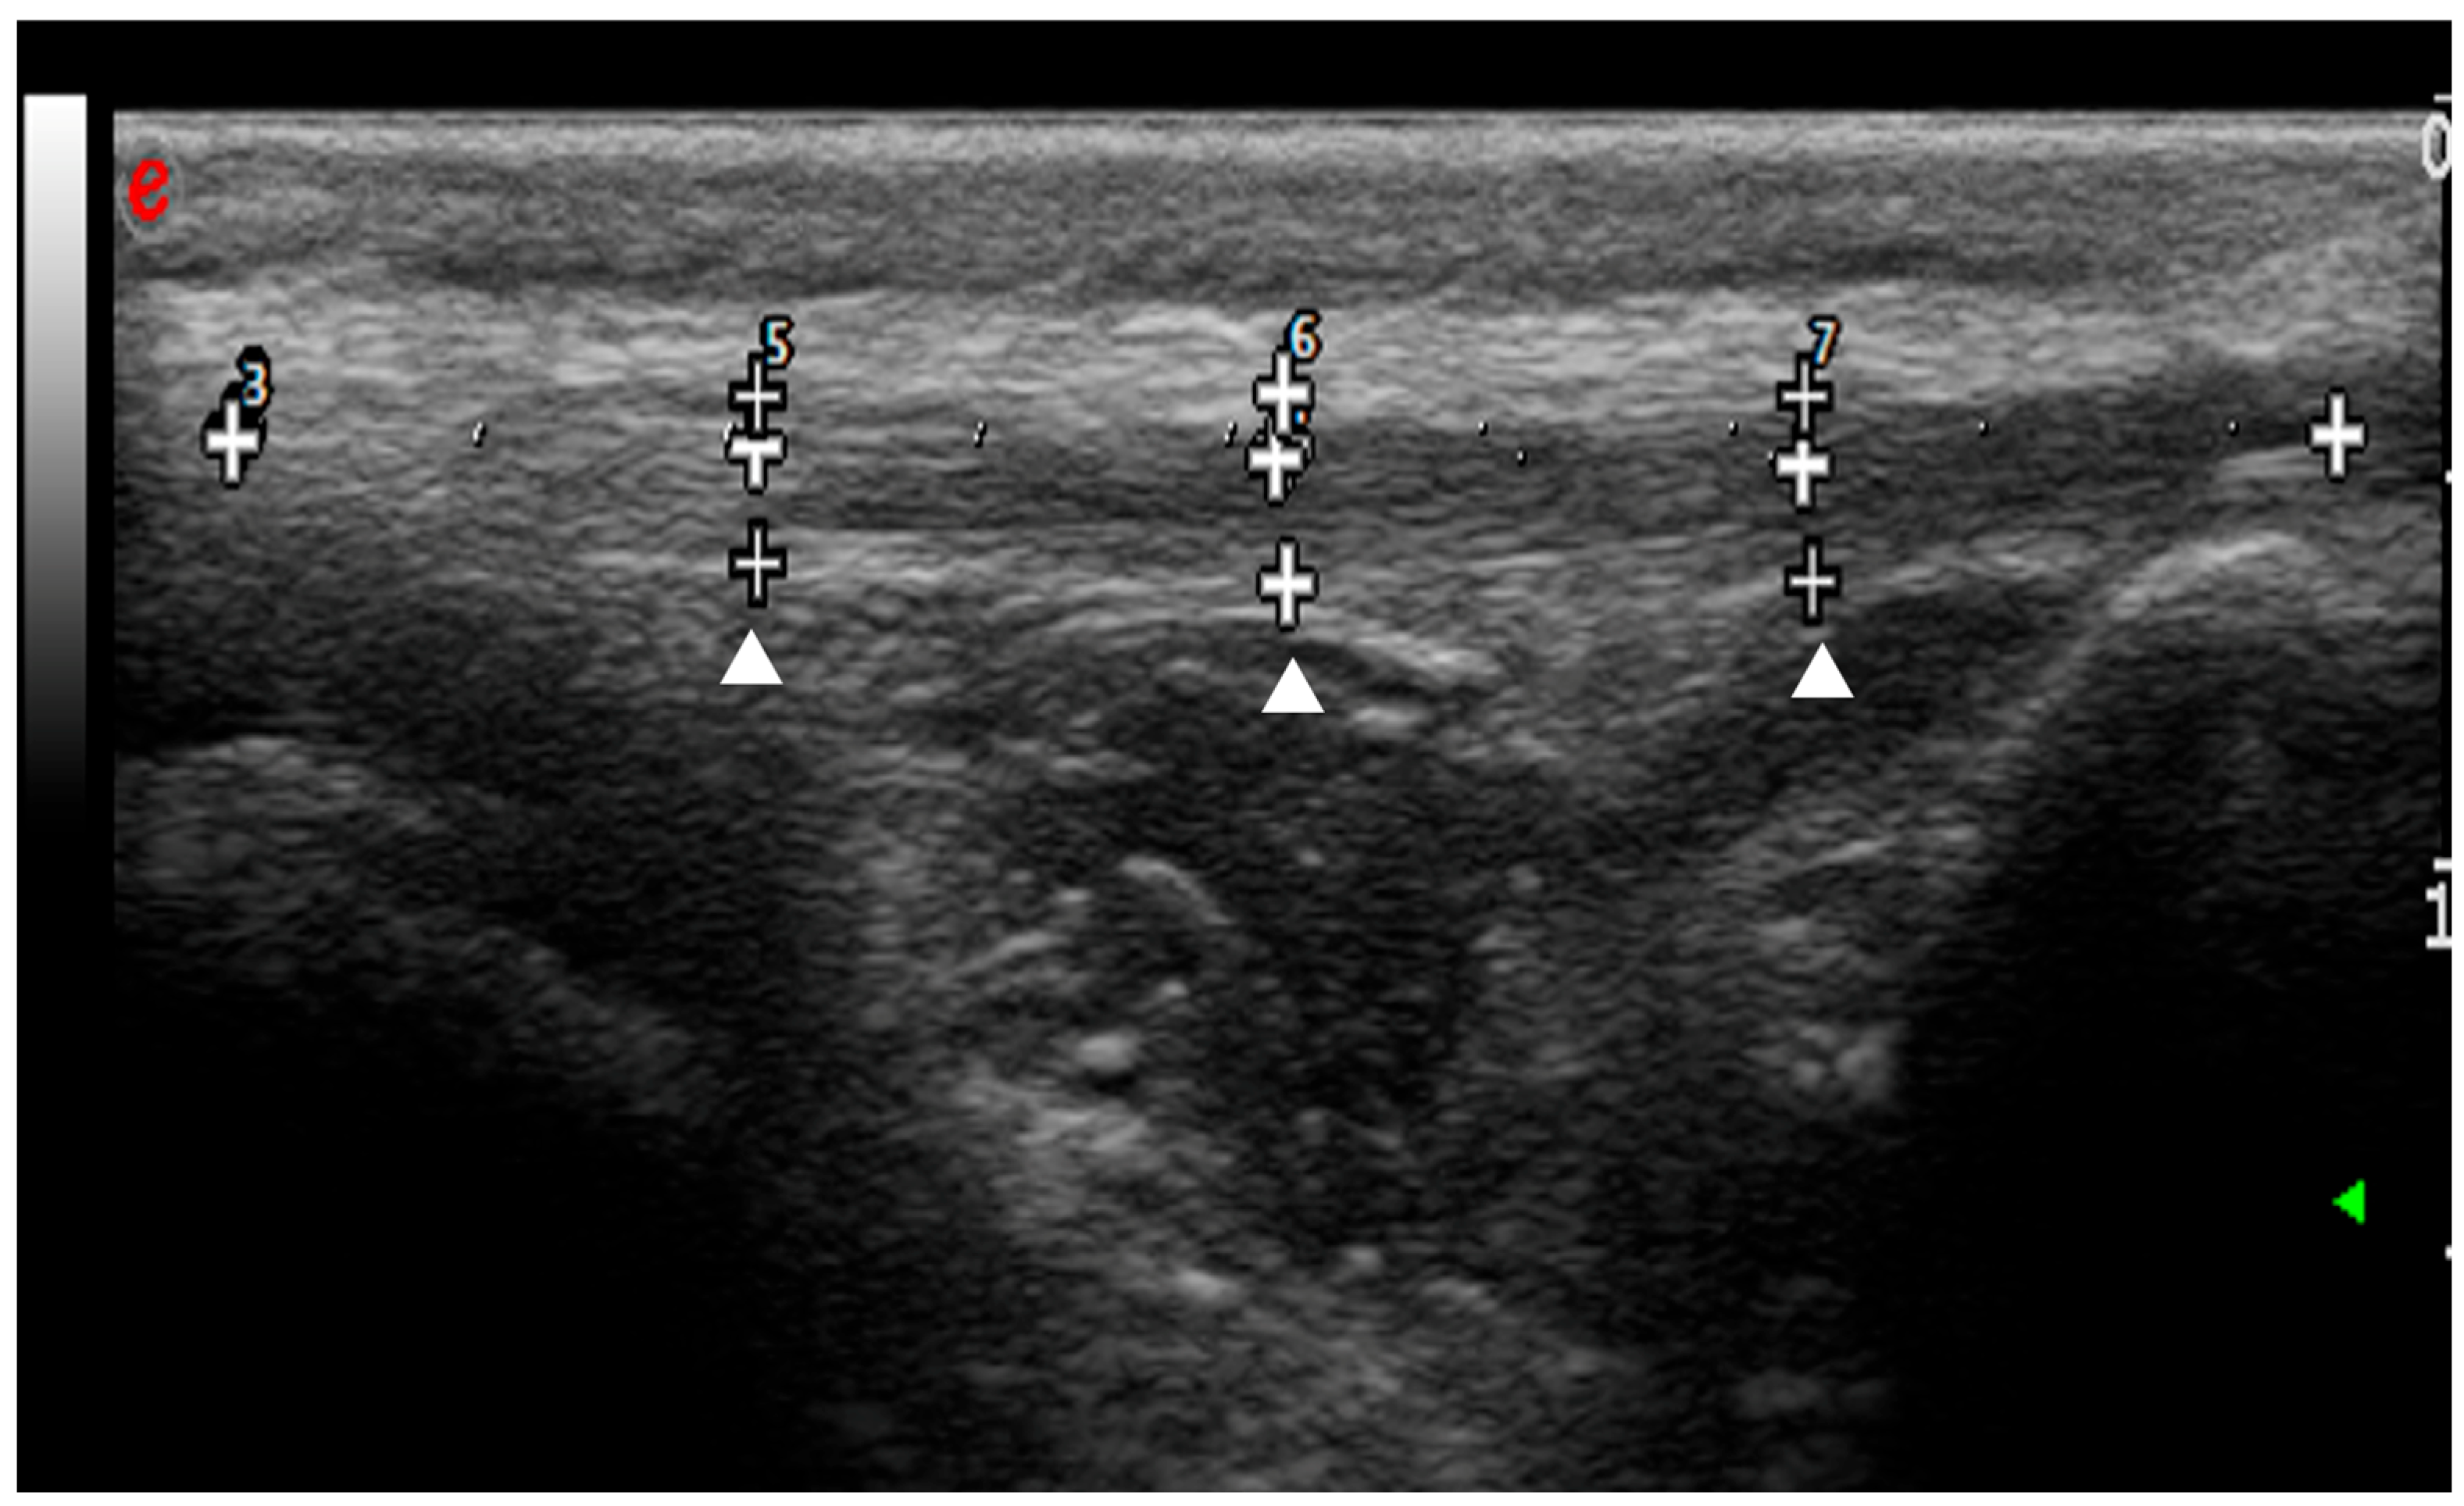

2.4. Ultrasonographic and Strain Elastosonographic Evaluations

3.2. Radiographic and Ultrasonographic Evaluations